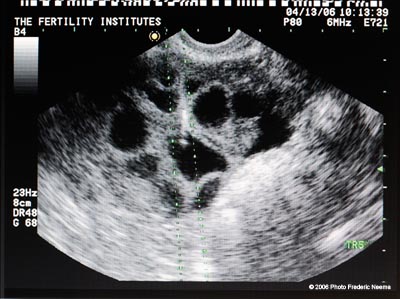

An ultrasound view of the patient's ovary. The volumes appearing in black are filled with fluid and are the follicules. In order for a follicle to develop, an egg must be present but the egg may not be isolated in every follicle due to the developmental process of oocyte maturation and normal degeneration. The Fertility Institutes uses Preimplantation Genetic Diagnosis (PGD) technology in conjunction with in-vitro fertilization to help couples to choose the sex of their future babies with a 99% success rate.